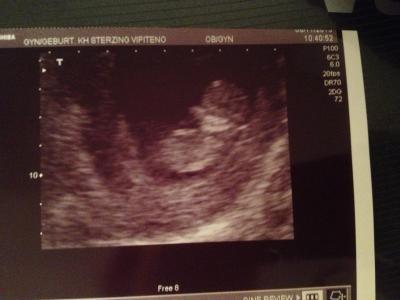

Hallo Mädels, melde mich wieder frisch und munter zurück vom Urlaub :-)! Ging leider viel zu schnell vorbei!!! War heute dann auch beim FA, Baby geht es so weit man sehen konnte super, US Auflösung ist nicht die beste.... Ist jetzt stolze 4,5 cm gross, also genau richtig für 11+1!! Bin sooo happy!!! Jetzt kann es auch jeder wissen, kann meinen Bauch nämlich schon nicht mehr verstecken u bin mega stolz darauf! Nur die Nackenfalte konnte er nivht messen.., habe den nächsten Termin am 04.12., kann man diese da dann noch messen?! Lg u ein wunderschönes Wochenende!!!

Bild zu FA bericht - Forum für Mai - Mamis